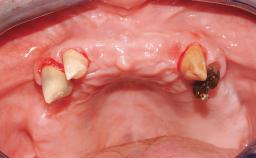

Iliac-Crest Block for Vertical and Horizontal Space Filling in the Anterior Maxilla

A 31-year-old man presented to our clinic 30 days after a motor vehicle accident in which he had suffered a dentoalveolar fracture in the anterior maxilla, including avulsion of teeth 12 and 11 and luxation of tooth 21. He was first treated on the night of the accident in a small city hospital with no oral and maxillofacial surgeon on the staff. A wired retention had been applied and the teeth repositioned to the best of the clinicians’ abilities. When he first presented to our care, the patient showed extrusion of teeth 12 and 11 associated with gingival recession due to bone loss in the anterior maxilla, and the stainless steel wires were still present.

Bone Volume Horizontally and vertically sufficient Horizontally deficient Deficient vertically or deficient vertically AND horizontally

Bone Volume Deficient vertically or deficient vertically AND horizontally

Soft Tissue Contour and Volume Significantly deficient